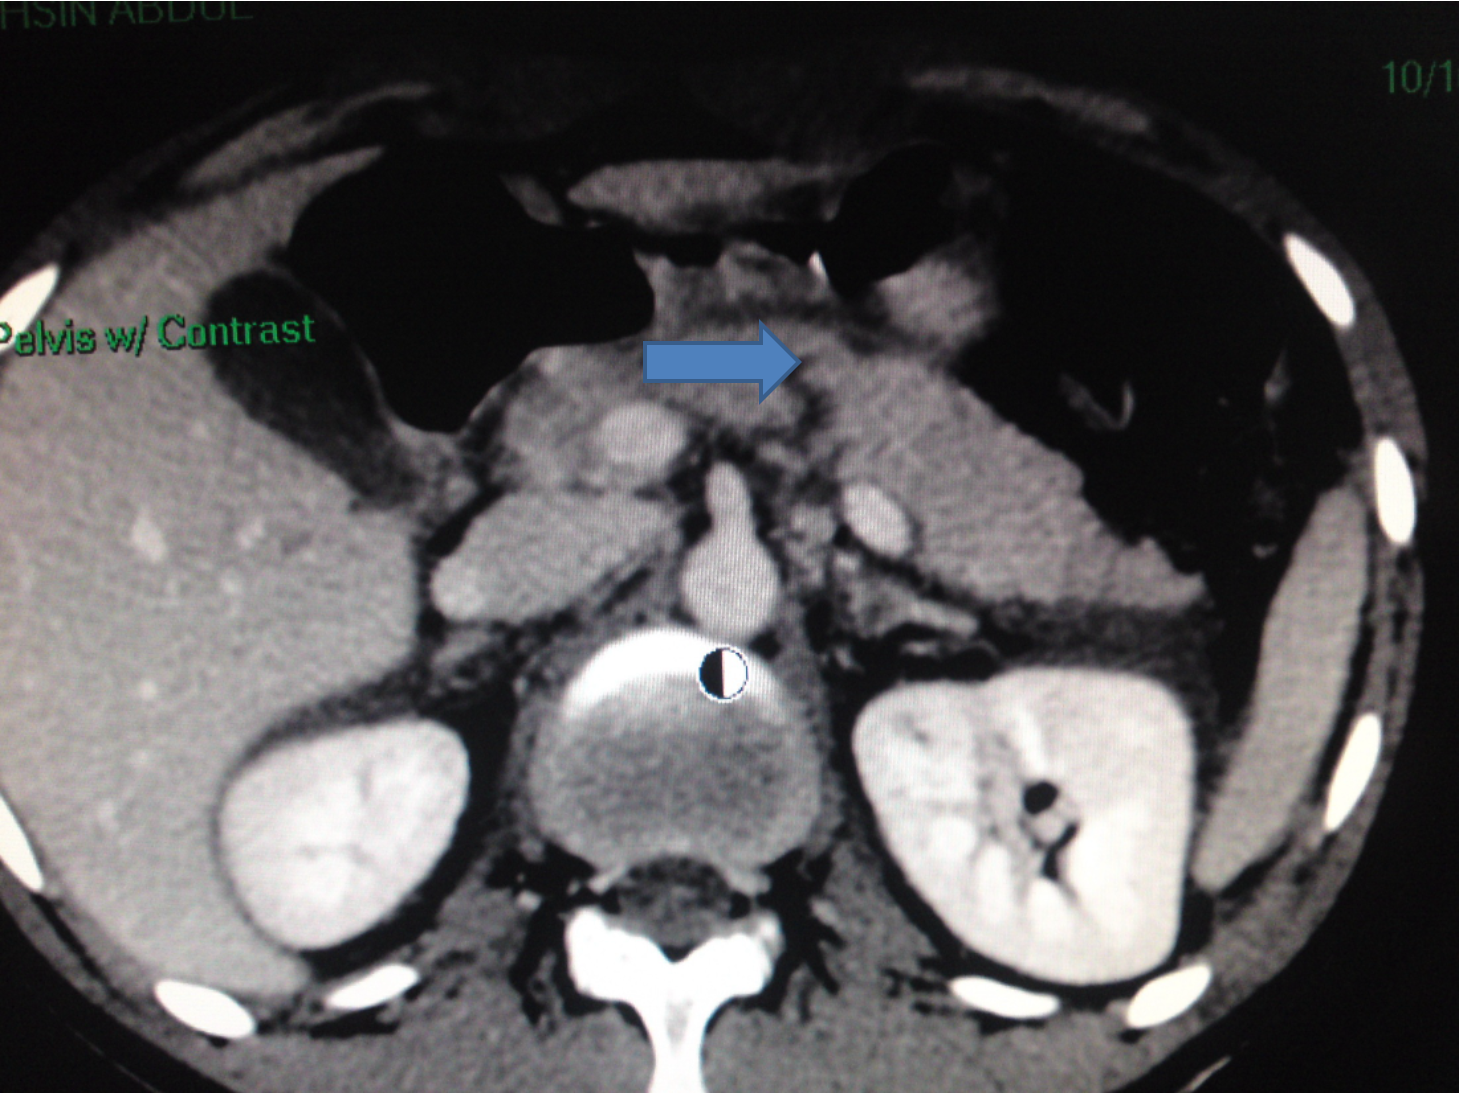

Pancreatic injuries

Diagnosis: difficult

- U/S, CT scan, elevated serum amylase may help